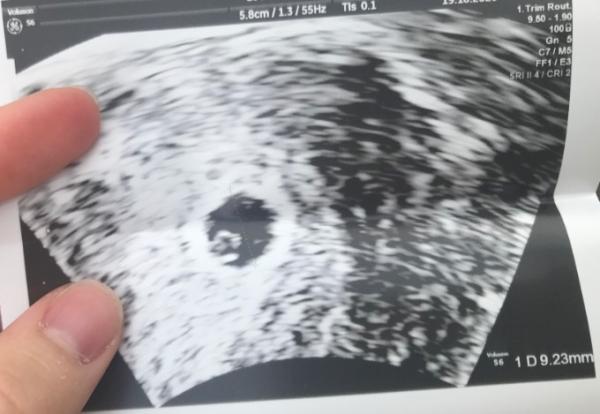

Hallo Mädls , war schon beim FA ... alles so wie es sein soll ! Fruchthöhle und Dottersack waren schon zu sehen nächste woche habe ich wieder am Dienstag Kontrolle und da gibt es dann den Mutterkindpass und eine genaue Untersuchung

Bild zu Update - Forum für Juni - Mamis